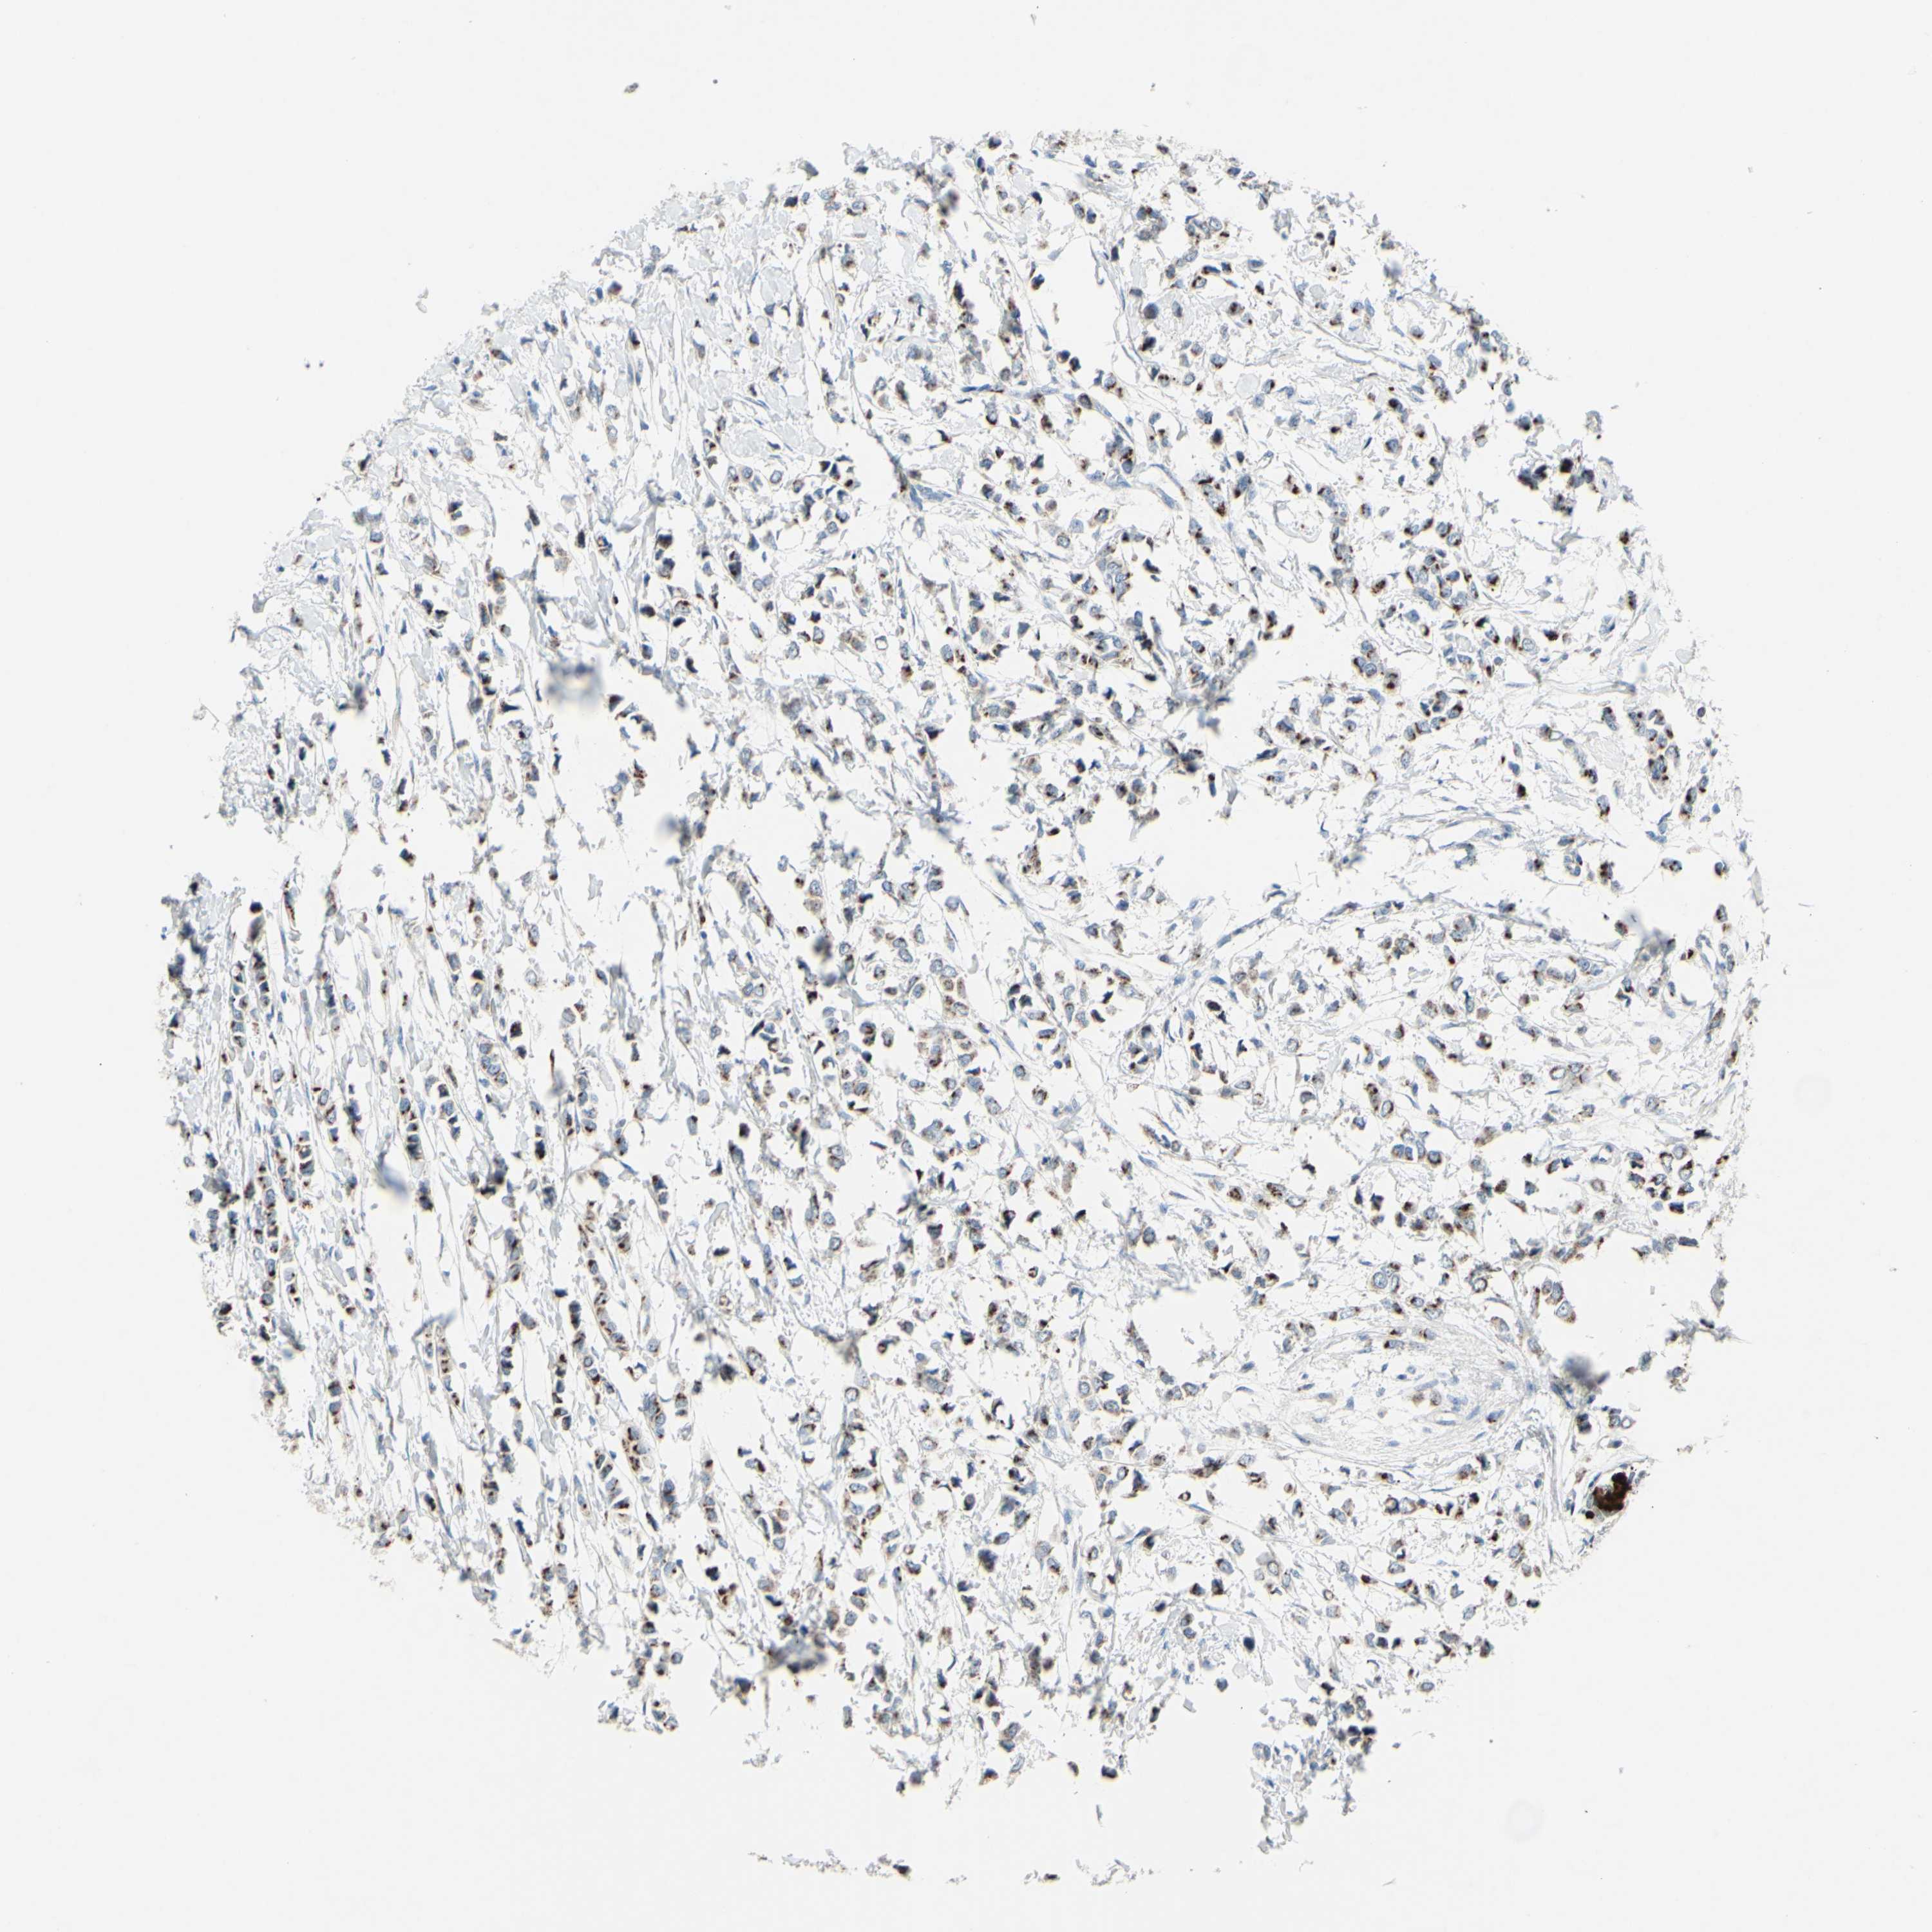

BRCA TCGA BRCA VALIDATION PROTEIN EXPRESSION

Breast cancer

Human cancer